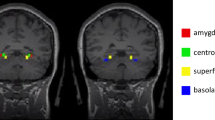

The inconsistency in findings of higher and lower connectivity between these regions in this review may be due to recent evidence in both controls and in varying clinical samples demonstrating the importance of examining subregions of the amygdala (including the centromedial, basolateral, amygdalostriatal, and superficial complex) and their connectivity patterns rather than examining the amygdala as a whole. Evidence of disturbances in the fear circuitry in only specific subregions of the amygdala has been demonstrated in clinical groups (e.g., autism spectrum disorder, post-traumatic stress disorder, major depressive disorder) and in controls [42,43,44,45]. For example, hyperconnectivity between the amygdala and the PFC was only found when looking at the centromedial complex (rather than basolateral or superficial complex) in people with autism spectrum disorder (vs. controls) [42]. In this review, one of the studies contributing to evidence of hyperconnectivity between the amygdala and PFC used amygdala subregions as seeds and found no evidence of hypoconnectivity [46]. Further research examining amygdala subregion connectivity with the PFC in those with SAD may be needed to clarify this aspect of the fear circuitry in SAD.

An alternative explanation for the inconsistent findings regarding higher and lower connectivity between the amygdala and frontal regions may be due to our grouping of frontal regions as one area. The frontal lobe is thought to be structurally and functionally divided into separate regions with different connectivity patterns, and structural and functional divisions [47]. A clearer pattern of connectivity between the amygdala and frontal regions arises when frontal regions are examined as smaller subdivisions. For example, looking specifically at the dorsomedial PFC, there were consistent reports of higher connectivity between this region and the amygdala. Notably, this is shown to be associated with increased self-directed criticism and an increased tendency to exaggerate the significance of potentially self-relevant stimuli from external threat cues in those with SAD [48, 49]. Another example of the usefulness of looking at specific frontal regions is by examining the rostral medial PFC, with consistent reports of lower connectivity between this region and the amygdala in those with SAD compared to controls. Previous research suggests that a decrease in connectivity between these regions is associated with increased social interactional anxiety and decreases in emotion regulation [50]. These findings highlight the importance of considering the various smaller individual subregions of the frontal lobe when examining and interpreting findings, given the number of structurally and functionally different regions that exist. However, discrepancies in how divisions are defined and analyzed could lead to difficulty in the synthesis of findings across studies.